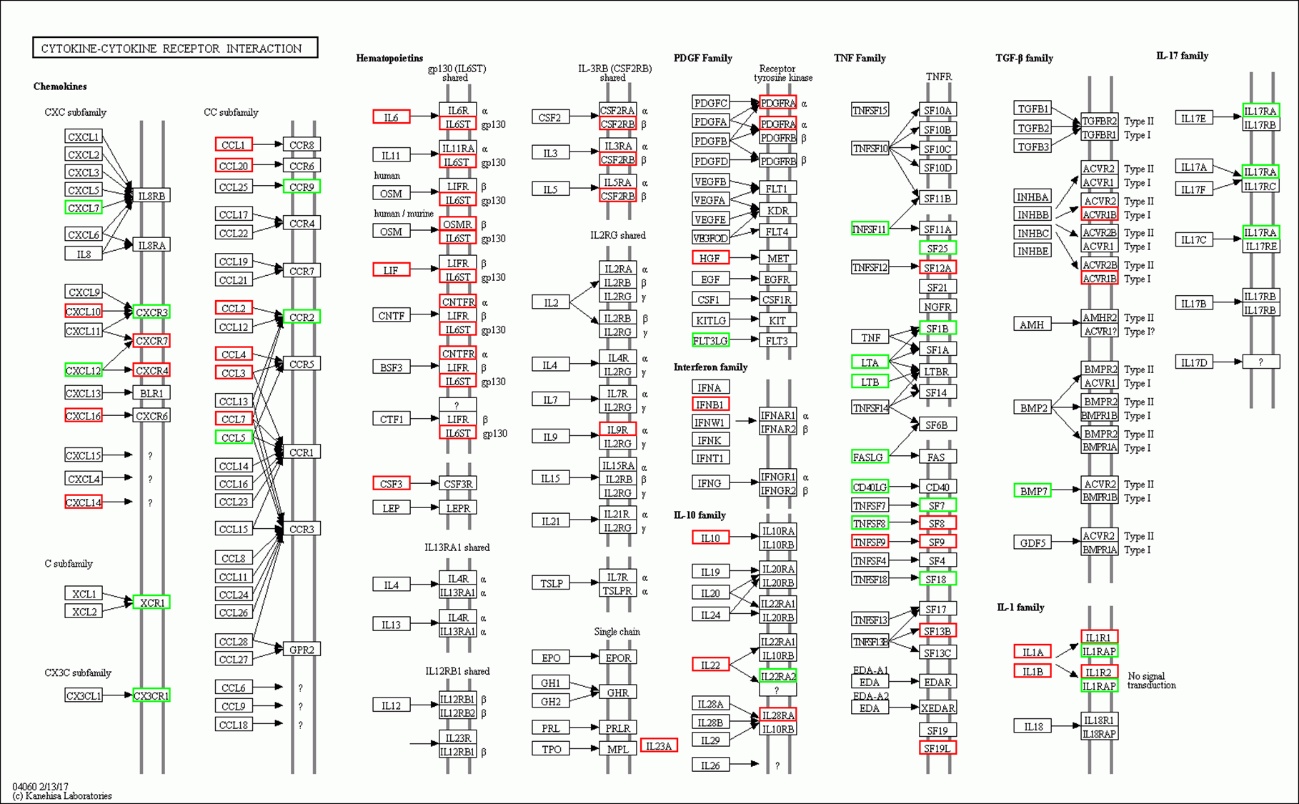

2 结果48 h各组病理结果,对照组脾组织结构正常(见图 1A )。脓毒症组脾组织见白髓结构破坏,红白髓交界模糊,多量组织细胞浸润,红髓充血(见图 1B)。差异mRNA的Volcano-plot分布图(见图 2)。相比于对照组,24 h时脓毒症组脾组织mRNA表达上调的有1 030个,下调的有935个[5];48 h组表达上调的有1 354个,下调的有1 763个。差异mRNA的聚类情况(见图 3)。GO功能分类结果(见图 4)。脓毒症大鼠脾组织部分通路相关基因表达情况(见图 5、6):脓毒症大鼠24 h,48 h脾组织关于细胞因子及其受体相互作用通路相关基因的分布图(见图 7,图 8)。脓毒症大鼠24 h,48 h脾组织关于细胞凋亡相关通路的基因分布图(见图 9,图 10)。

| 注:红色:上调基因,绿色:下调基因。 图 7 脓毒症大鼠24 h组 |

(1)细胞与其受体相互作用信号通路相关的基因表达上调数明显减少,部分甚至转为下调。从图 7、8可以看出脓毒症大鼠24 h脾组织mRNA表达上调,而48 h转为下调的有2个:CXCL10、CCL1;从上调转为正常表达的有22个:CXCL16、CNTFR、IL9R、IL23A、HGF、IFNB1、IL22、PDGFRA、IL28RA、TNFSF9、SF12A、SF9、SF19L、IL1β、ACVR1B、CXCR7、CXCR4、IL6、LIF、CSF3、IL6ST、CCL4。从正常表达转为下调的有30个:CXCL9、CXCL11、CXCL4、CCL21、CCR7、OSM、IL12、IL11RA、IL15、IL3RA、IL2RB、EPOR、PDGFA、VEGFA、VEGFOD、FLT1、KDR、KIT、FLT3、TNFSF10、SF11A、NGFR、SF14、CD40、TGFB1、TGFB2、TGFB3、IL17RC、IL17RE、BLR1。而从表达下调转为上调的仅一个:IL17RA,从下调转为正常表达的仅2个:FASLG、TNFSF8,从正常表达转为上调的有10个:CCR1、GPR2、CNTF、CSF3R、SF8、SF17、SF13B、IL1A、IL1R1、IL1R2。从中可以看出脓毒症早期细胞因子与其受体相关基因表达以上调为主,脓毒症晚期则相反,部分基因转为下调,部分基因转为正常表达,多数正常表达基因在晚期出现表达下调符合脓毒症早期过度炎症反应、晚期免疫抑制的观点。